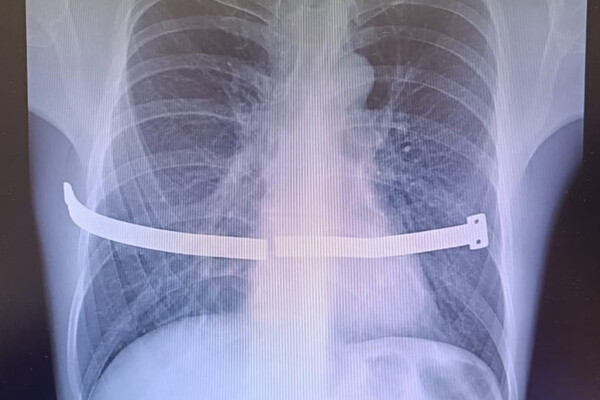

У россиянина разломилась в груди пластина, которую он должен был удалить 13 лет назад

В Сургуте врачи спасли мужчину с разломившейся пластиной в грудной клетке

Врачи Сургутского травматологического центра спасли мужчину, беспечность которого едва не привела к серьезным повреждениям внутренних органов. Случаем из практики поделились в пресс-службе медицинского учреждения.

Пациент 17 лет проходил с металлической пластиной в груди, которая, ожидаемо, раскололась, так как не была предназначена для столь долгой «эксплуатации». Конструкцию установили мужчине для коррекции воронкообразной деформации груди. Устройство следовало удалить спустя четыре года, но пациент не торопился с операцией. В итоге пластина разломилась пополам и один из ее краев стал упираться в оболочку сердца.

Из-за сильных болей пациент обратился к медикам, и операции избежать не удалось.

«Пациент все-таки расстался с пластиной. Хирурги успешно извлекли ее, несмотря на технические сложности. За многие годы металл уже сросся с костной тканью, пришлось частично резецировать ребро», — рассказали в пресс-службе, отметив, что это не повлияет на качество жизни.

Медики отметили, что подобные вмешательства малотравматичны и мужчина зря подвергал себя рискам, отсрочивая ее.